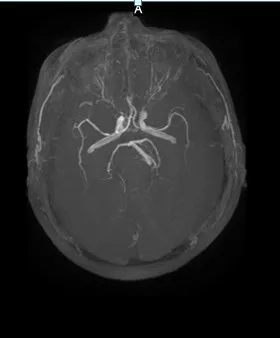

头颅MRI+MRA(2018-01-30日)